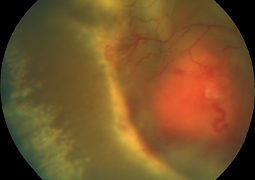

- Radiation Maculopathy in Patients with Malignant Melanoma of the Corpus Ciliare and Choroidea Following One-Day Session of Stereotactic Radiosurgery